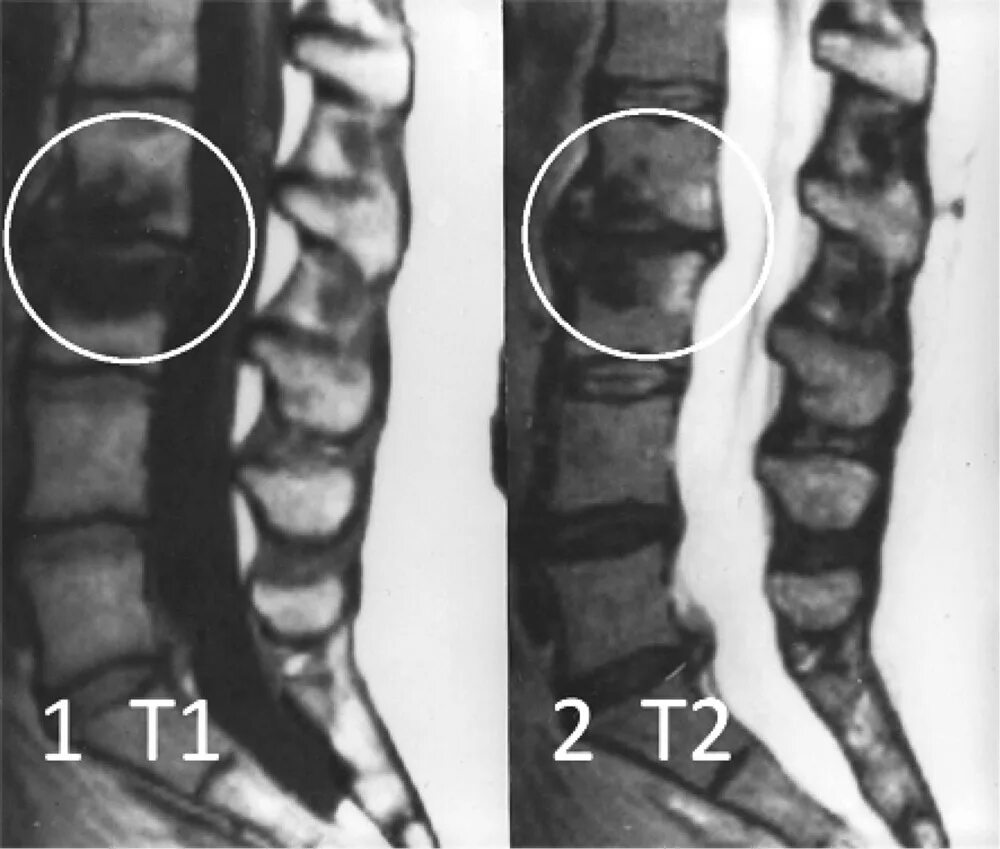

Изменения по типу modic 1